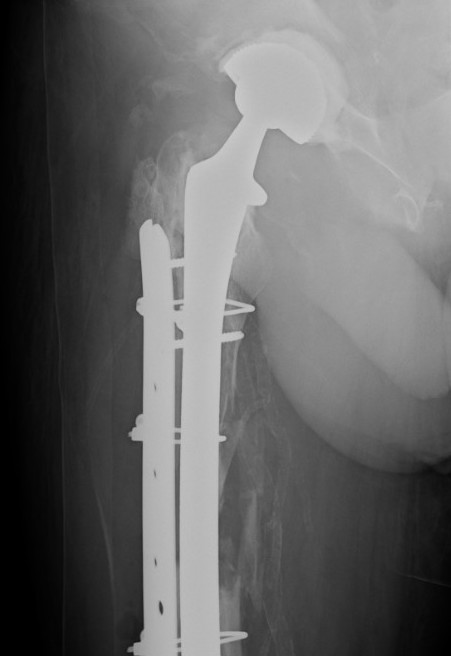

Long stem uncemented revision

Revision uncemented arthroplasty with Zimmer cable plate

Long stem uncemented revision with cortical strut allograft

Long stem uncemented revision with plate + cortical struts